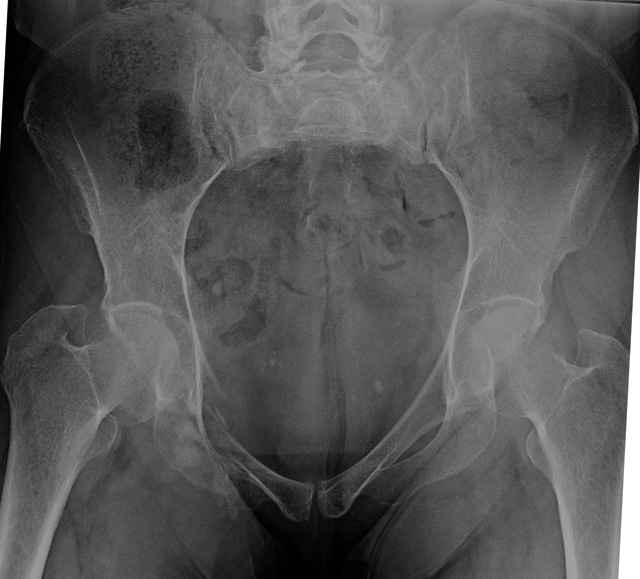

54 yo Female Fell c/o Pain

Initial Films

3 Months After Fall

Continued Pain & Immobility

(+) Instability to Compressive Manual Exam

Pelvic CT Scan - 3 Months After Fall

Sacral Injuries

Ramus Fractures